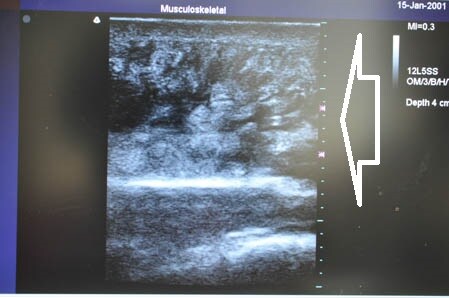

ではいつものように3Dタッチビュー(=超音波)で

皮下脂肪層を確認しながら見ていきましょう。

左ちからこぶ。

↓ ↓ ↓